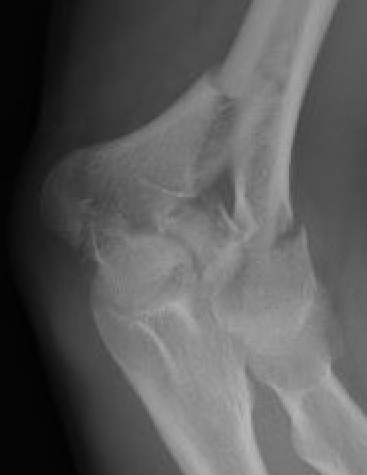

Nonunion in a proximal humerus shaft fracture treated nonoperatively